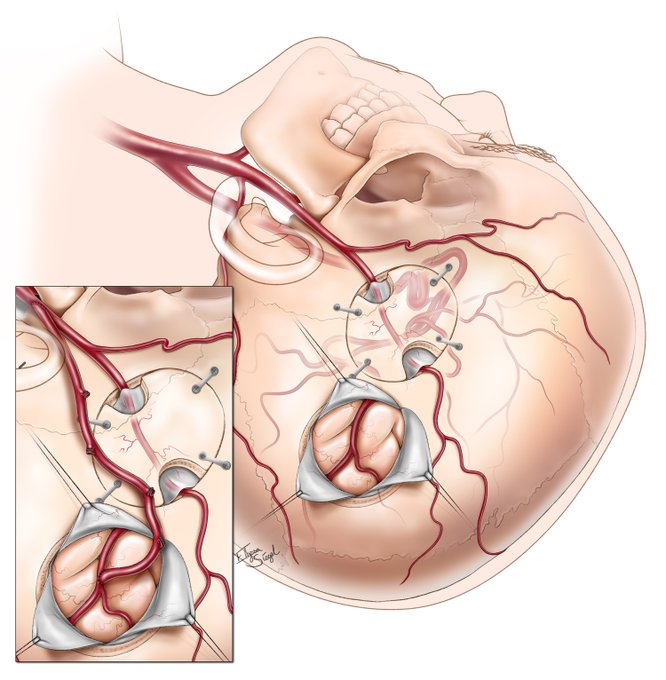

Failed indirect (EDAS) bypass with recurrent strokes in a moyamoya patient may require a complex revascularization solution.

We describe a salvage bypass using an interposition graft.(Great Illustrations-Elyssa Siegel) https://t.co/HNMppbS66O

@moyamoyafdn @eytanraz @neuroangio1